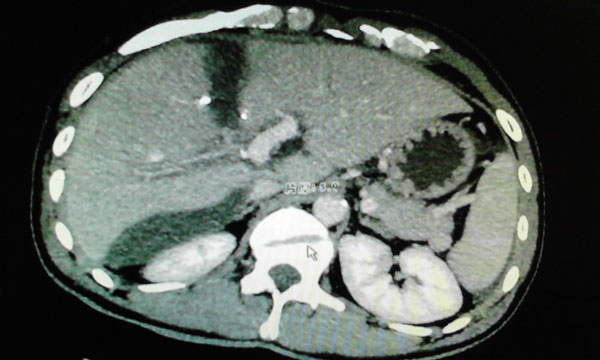

经过全面、详细的检查,黄先生被确诊为原发性肝癌,医生发现肿瘤位于肝脏的ⅦⅧ段,侵犯肝右静脉,与肝中静脉关系密切,必须行右半肝全切除,只剩下左半肝,而且肿瘤将第2肝门严重挤压。

7月6日,卫生部肝胆肠中心的李年丰教授和我院肝胆外科主任韦杨年副教授及其团队主刀为患者手术。术中探查发现肿瘤位于肝脏ⅦⅧ段,大小约有8.0cm×5.0cm×5.0cm,左肝轻度硬化。在仔细探查后,韦主任为他施行了腹腔镜下门静脉右支结扎+肝脏离断术+胆囊切除术。

术中彩超检查

肿瘤的位置